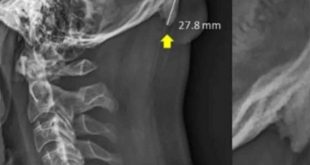

Una investigación publicada en la revista Journal of Anatomy reveló que el uso de los teléfonos celulares está provocando la salida de una especie de cuerno en el cráneo humano. David Shahar, científico encargado de la investigación, reveló que existe una tendencia al crecimiento de una pequeña protuberancia en forma …